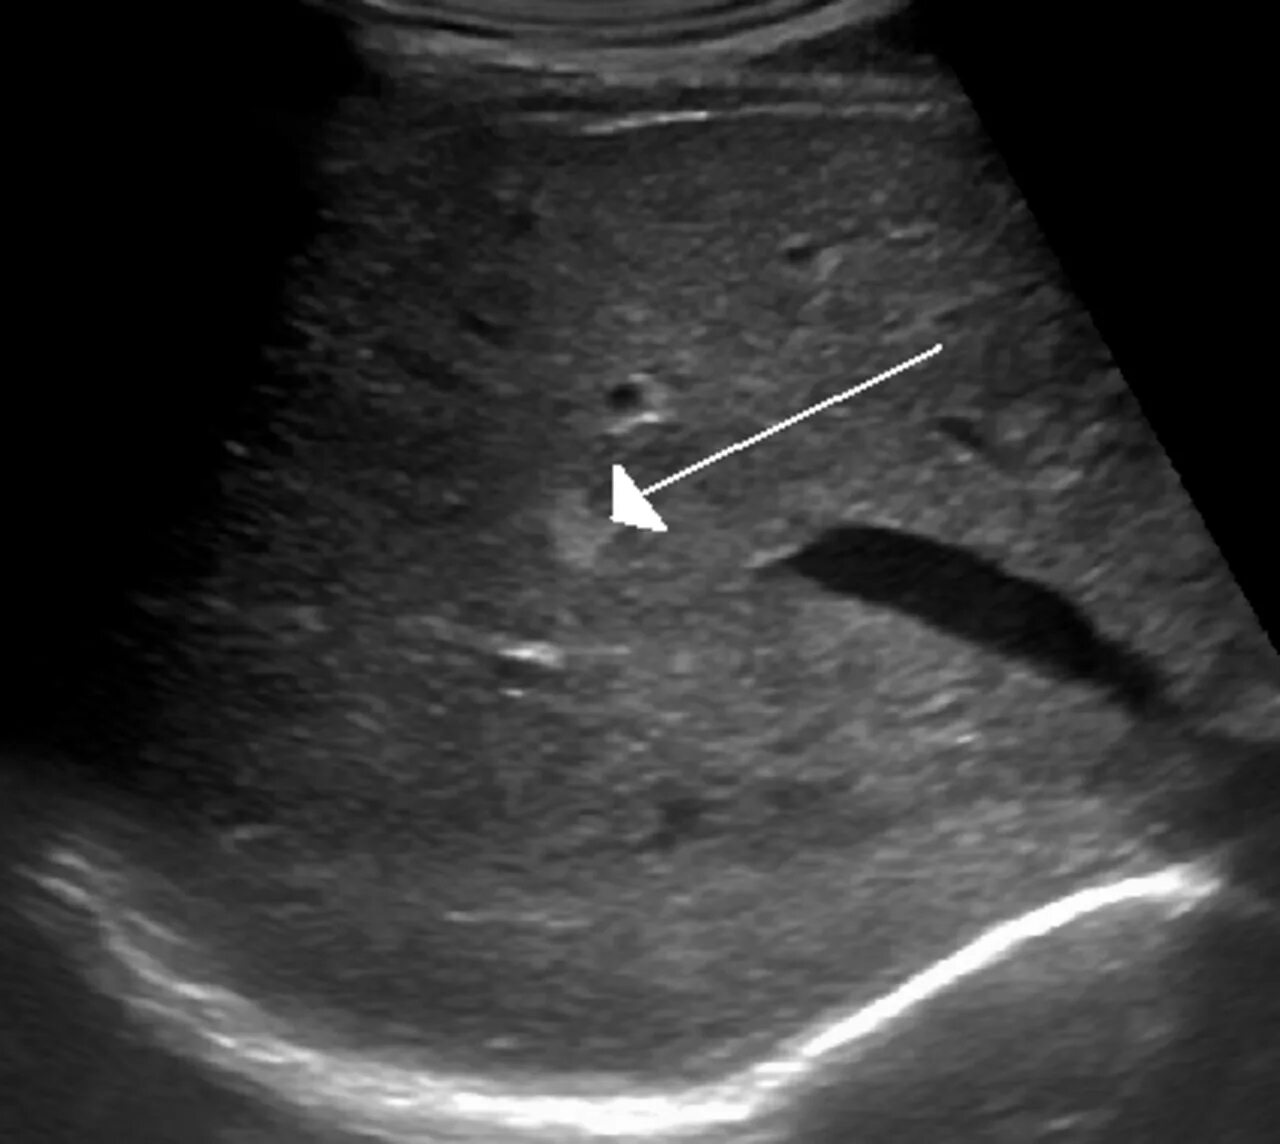

Лечение гемангиомы печени у взрослых